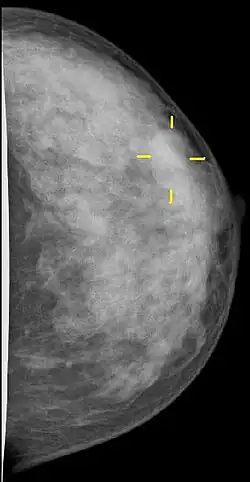

Die Röntgen-Mammographie ist einer S3-Leitlinie von 2010 zufolge zurzeit die einzige für die Erkennung von Brustkrebsvorstufen oder frühen Tumorstadien allgemein als wirksam anerkannte Methode.[91] Die Mamma-Kernspintomographie ist möglicherweise überlegen, jedoch für ein Massenscreening zu teuer.[92] In Deutschland wurde deshalb ein qualitätsgesichertes Mammographie-Screening-Programm auf der Grundlage der „Europäischen Leitlinien für die Qualitätssicherung des Mammographie-Screenings“ für Frauen von 50 bis 69 Jahren aufgebaut. Dazu wurde Deutschland in 94 Regionen aufgeteilt, für die jeweils eine Screening-Einheit verantwortlich ist.[93] 2024 wurde das Mammographie-Screening in Deutschland auf Frauen von 50 bis 74 Jahren ausgeweitet. In den USA gab es 2002 die Empfehlung, das Mammographiescreening bereits mit 40 Jahren zu beginnen.[88]

CAD-Systeme (Computer-assisted Detection) können den Radiologen bei der Auswertung der Mammographien unterstützen. Solche Untersuchungen können in den USA und den Niederlanden von den Krankenkassen bezahlt werden. Nach bisher veröffentlichten Studien verbessern die bislang verfügbaren Geräte die Erkennungsrate jedoch nicht.[95] In den europäischen Screeningprogrammen wird daher die Doppelbefundung durch zwei Ärzte (und durch einen dritten bei Auffälligkeiten) bevorzugt.

Die Mammographie ist bei Frauen mit dichtem Drüsengewebe in ihrer Aussagekraft begrenzt. Bei extrem dichtem Gewebe werden etwa 50 % der Brusttumoren mit der Mammographie nicht entdeckt. Dies betrifft in erster Linie jüngere Frauen, denen die Sonographie, im Einzelfall auch Kernspin-Mammographie, empfohlen wird. Nach systematischer Literaturrecherche bewertet der IGeL-Monitor (Initiator und Auftraggeber: MDS (Medizinischer Dienst des Spitzenverbandes Bund der Krankenkassen)) die Sonographie (Ultraschall) mit „unklar“, die Magnetresonanztomographie (MRT, Kernspin) mit „tendenziell negativ“. Die Wissenschaftler des IGeL-Monitors fanden in beiden Fällen keine Studien, die die Frage untersucht haben, ob die Untersuchungen Frauen tatsächlich davor bewahren können, an Brustkrebs zu sterben. Das gilt für die Untersuchungen zusätzlich zum Mammographie-Screening ebenso wie als Alternative zum Mammographie-Screening. Bei der MRT sind Schäden durch das Kontrastmittel möglich, das dabei gespritzt wird. Diese Bewertungen gelten für Frauen ab 40 Jahren, die kein erhöhtes Brustkrebs-Risiko haben.[96]